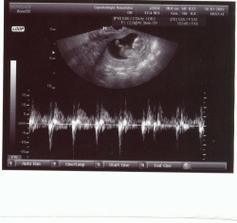

SRPŇÁTKA 2007 - fotky UTZ

album věnované mimískům, které se narodí v srpnu 2007 a jejich maminkám ze "Společného termínu SRPEN"